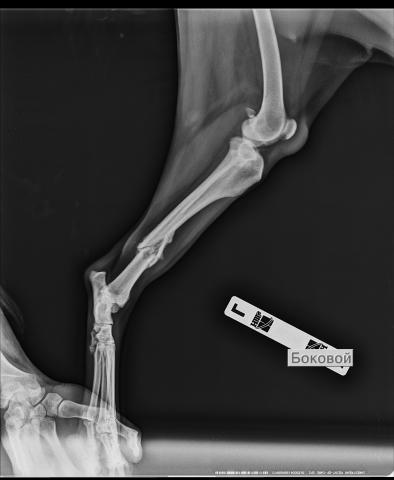

Здравствуйте. У меня собака хаски, 5 лет. 2 месяца назад сбила машина, был перелом задней левой лапы. Врач вставил штырь, который удалили спустя месяц, сейчас собака хромает, на лапку приступает но неуверенно. Показались к другому врачу, который сказал, что перелом в двух местах, а не в одном, как мы думали раньше и сказал срочно ставить пластины на сустав, потому что образовался ложный хрящ, который планируют срезать и зачищать. Первый врач говорит, что всё хорошо, что кость ещё не восстановилась и требуется время.Скажите пожалуйста, что всё таки делать.

С уверенностью могу сказать только то, что изначально тактика лечения собаки была выбрана неверная. Перелом сложный оскольчатый, и фиксация стержнем в таких случаях, как правило, не приводит к хорошему сопоставлению всех отломков. Перелом нужно было фиксировать либо пластинами, либо проволокой.

сейчас у Вас два варианта лечения: преложенный первым врачом и предложенный вторым. Оба они имеют право на существование и оба обоснованы. Но, как один, так и другой, имеют свои плюсы и минусы. Чтобы решить, какой тактике (пассивной выжидательной или активной оперативной) отдать предпочтение, нужно, как минимум, хорошо рассмотреть рентгеновский снимок (его видно плохо). В идеале же хотелось бы увидеть все снимки за время лечения.

И еще. Я не ветеринар, я хирург человеческий, поэтому не сильно знаком с современными методиками лечения в ветеринарной травматологии. Если бы речь шла о человеке, то дальнейшая тактика - это фиксация перелома аппаратом ВЧКДО (более известен как аппарат Илизарова). Из того, что Вам предложили, наиболее предпочтительным вариантом (с моей точки зрения) все же выглядит повторная операция.